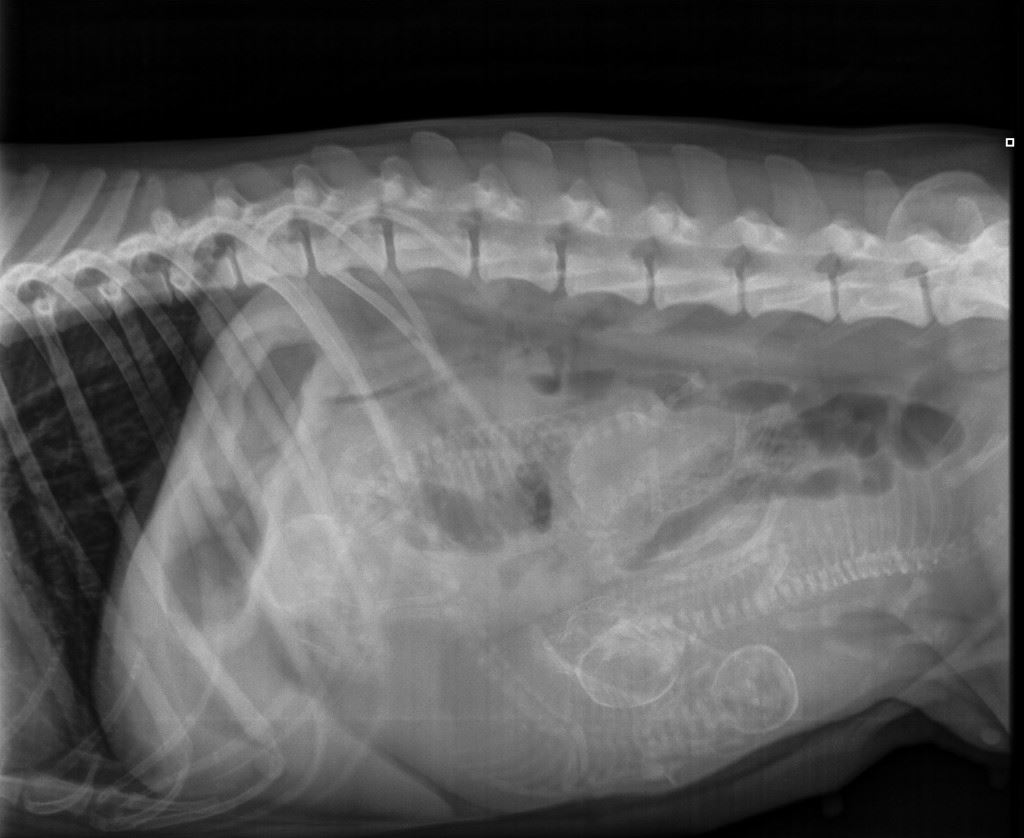

Viralliset selkäkuvat |

Välimuotoinen lanne-ristinikama: LTV0 (normaali) |

Muu luusto *) | Selkäranka, polvet ja olkapäät OK | Selkäranka ja olkapäät OK, polvet 0/0 | - | Selkäranka, polvet ja olkapäät OK | Selkäranka ja olkapäät OK, polvet 0/0 |

*) 6 koiran (muut paitsi Pikimusta ja Parfyymi) luustokuvaukset tehtiin 19.3.10 ell Kari Ventelän toimesta.

Kuvatuissa nivelissä ja selkärangassa ei havaittu muutoksia.